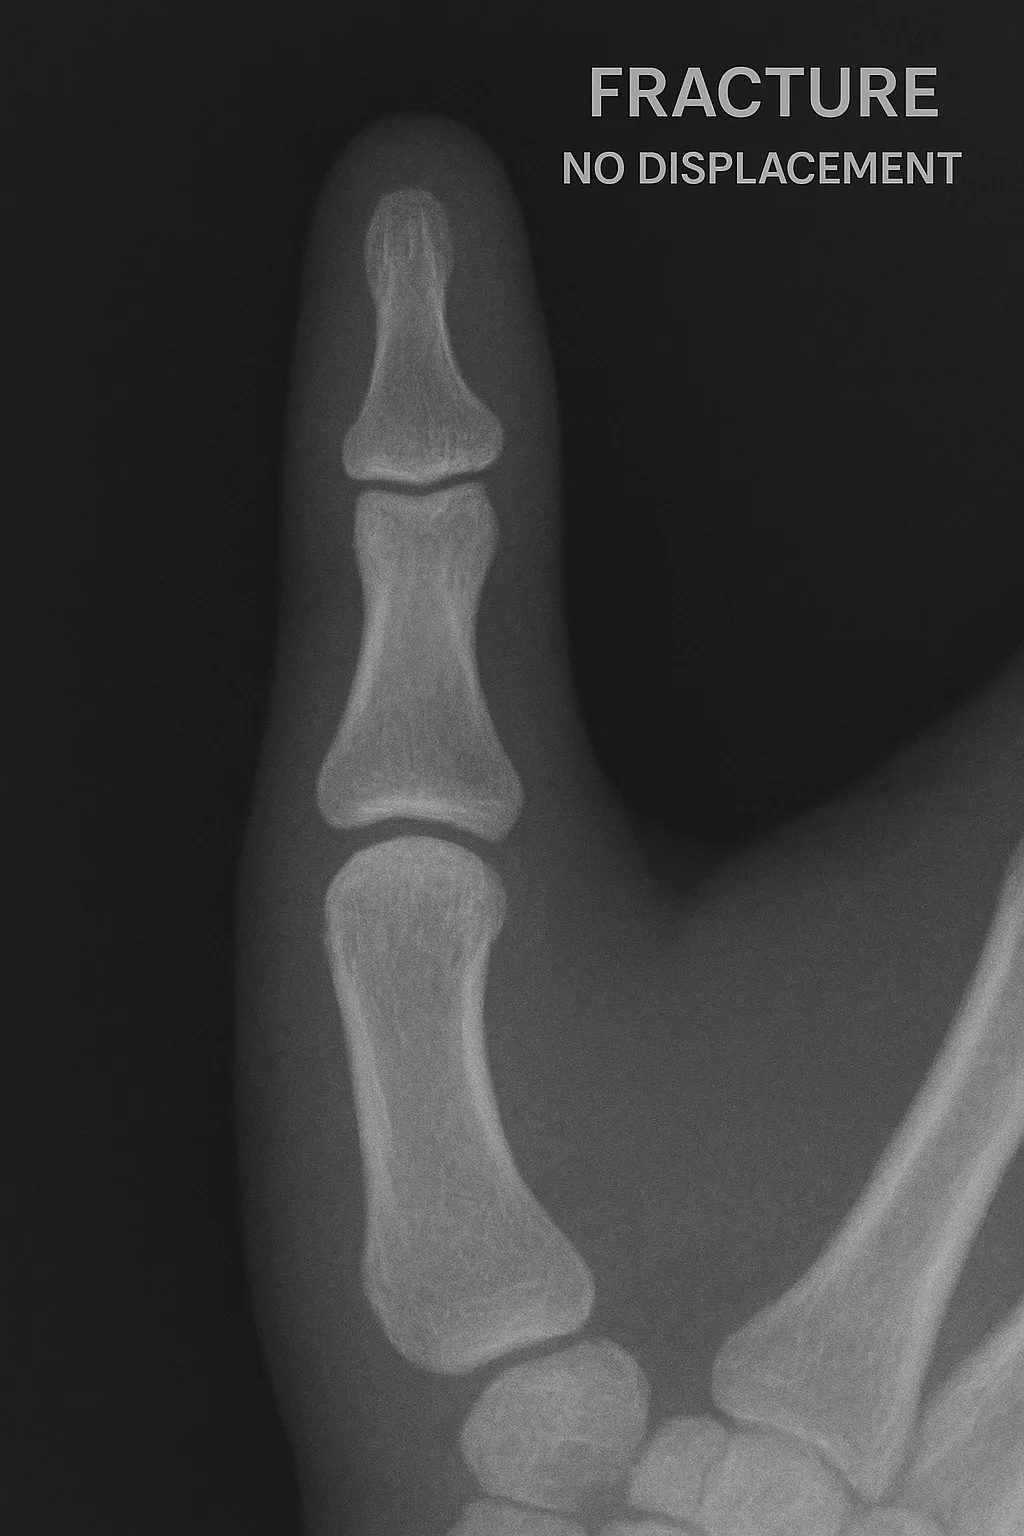

翌日, 右母指のX線写真を撮ったところ, 右母指の末節骨が中央で横に骨折していました.

幸いズレは少なく, ギプスなどで固定しないで(爪が副え木代わりになるので)安静を保てば, 治ると判断しました.